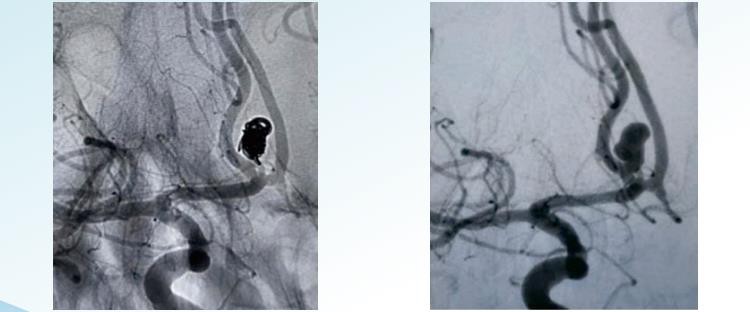

ΡενόβαΥΔΤο αποσπώμενο σύστημα περιέλιξης ανευρύσματος προσφέρει τυχαίες, ελικοειδείς και τρισδιάστατες αποσπώμενες επιλογές για ενδαγγειακό εμβολισμό σε διαμέτρους από 1 έως 22 m. Έχει σχεδιαστεί για να εμβολίζει τα ανευρύσματα από το πλαίσιο μέχρι το τέλος και περιλαμβάνει πηνία διαμορφωμένα ειδικά για την επίτευξη ομόκεντρης πλήρωσης ανευρύσματος και σπείρες μεγάλου όγκου για την επίτευξη υψηλής πυκνότητας συσσώρευσης. Η τυχαία περιέλιξη είναι η απλούστερη και παλαιότερη μορφή τεχνικής περιέλιξης ανευρύσματος. Περιλαμβάνει την εισαγωγή ενός μόνο πηνίου ή μιας ομάδας σπειρών στο ανεύρυσμα. Τα πηνία είναι συνήθως κατασκευασμένα από πλατίνα και είναι λεπτά και σφιχτά κουλουριασμένα για να μην δημιουργούνται κενά ή κενά στον σάκο. Η ελικοειδής περιέλιξη περιλαμβάνει τη χρήση ενός μακρύτερου, λεπτού σύρματος που τυλίγεται γύρω από τον εαυτό του με ελικοειδές τρόπο, σχηματίζοντας μια δομή που μοιάζει με ελατήριο. Το σύρμα εισάγεται μέσα στο ανεύρυσμα σε ισιωμένη μορφή και μόλις εισέλθει, αφήνεται να σπειρωθεί και να διασταλεί για να γεμίσει τον σάκο του ανευρύσματος. Οι ελικοειδείς σπείρες είναι ευρύτερες και πιο στενά συσκευασμένες από τις τυχαίες σπείρες, παρέχοντας έτσι καλύτερη απόφραξη του ανευρύσματος. Το τρισδιάστατο πηνίο περιλαμβάνει τη χρήση ενός ειδικά σχεδιασμένου πηνίου, το οποίο κατασκευάζεται χρησιμοποιώντας μια ηλεκτρονική διαδικασία απεικόνισης που δημιουργεί ένα ακριβές τρισδιάστατο μοντέλο του ανευρύσματος. Το πηνίο κατασκευάζεται για να ταιριάζει με το ακριβές μέγεθος και σχήμα του ανευρύσματος. Αυτός ο τύπος πηνίου έχει σχεδιαστεί για να εφαρμόζει άνετα στον σάκο του ανευρύσματος, παρέχοντας εξαιρετική απόφραξη και μειώνοντας τον κίνδυνο επιπλοκών. Τα τρισδιάστατα πηνία είναι ιδιαίτερα αποτελεσματικά στη θεραπεία ανευρυσμάτων που είναι δύσκολο να προσεγγιστούν ή σε εύθραυστα αιμοφόρα αγγεία.

ΡενόβαΥΔ3D Αποσπώμενα πηνία

ΡενόβαΥΔΕλικοειδή αποσπώμενα πηνία